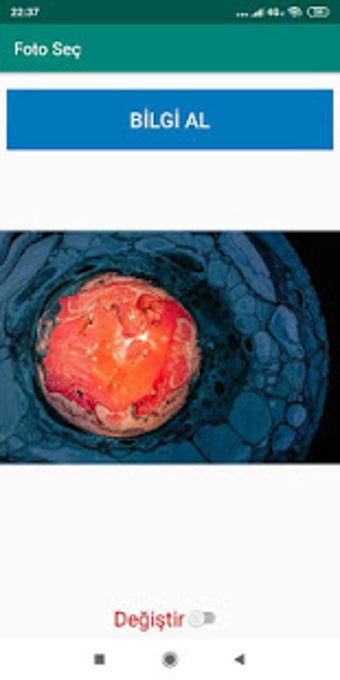

SERSER tarafından Android için ücretsiz bir uygulama.

Foto Seç, 'Yardımcı Programlar ve Araçlar' kategorisinin bir parçası olan Android için ücretsiz bir uygulamadır.

Android için Foto Seç Hakkında

Bu yazılım 18 Haziran 2019'da Softonic'te yayınlandı ve henüz test edemedik.

Denemenizi ve bize bir yorum bırakmanızı veya web sitemizde buna değer vermenizi öneririz. Bu, diğer kullanıcılarımıza çok yardımcı olacaktır!

Foto Seç, Android 9.0 veya üzeri sürümlerde çalışır. Programın güncel sürümü 1.0 olup, sadece Türkçe olarak edinebilirsiniz.